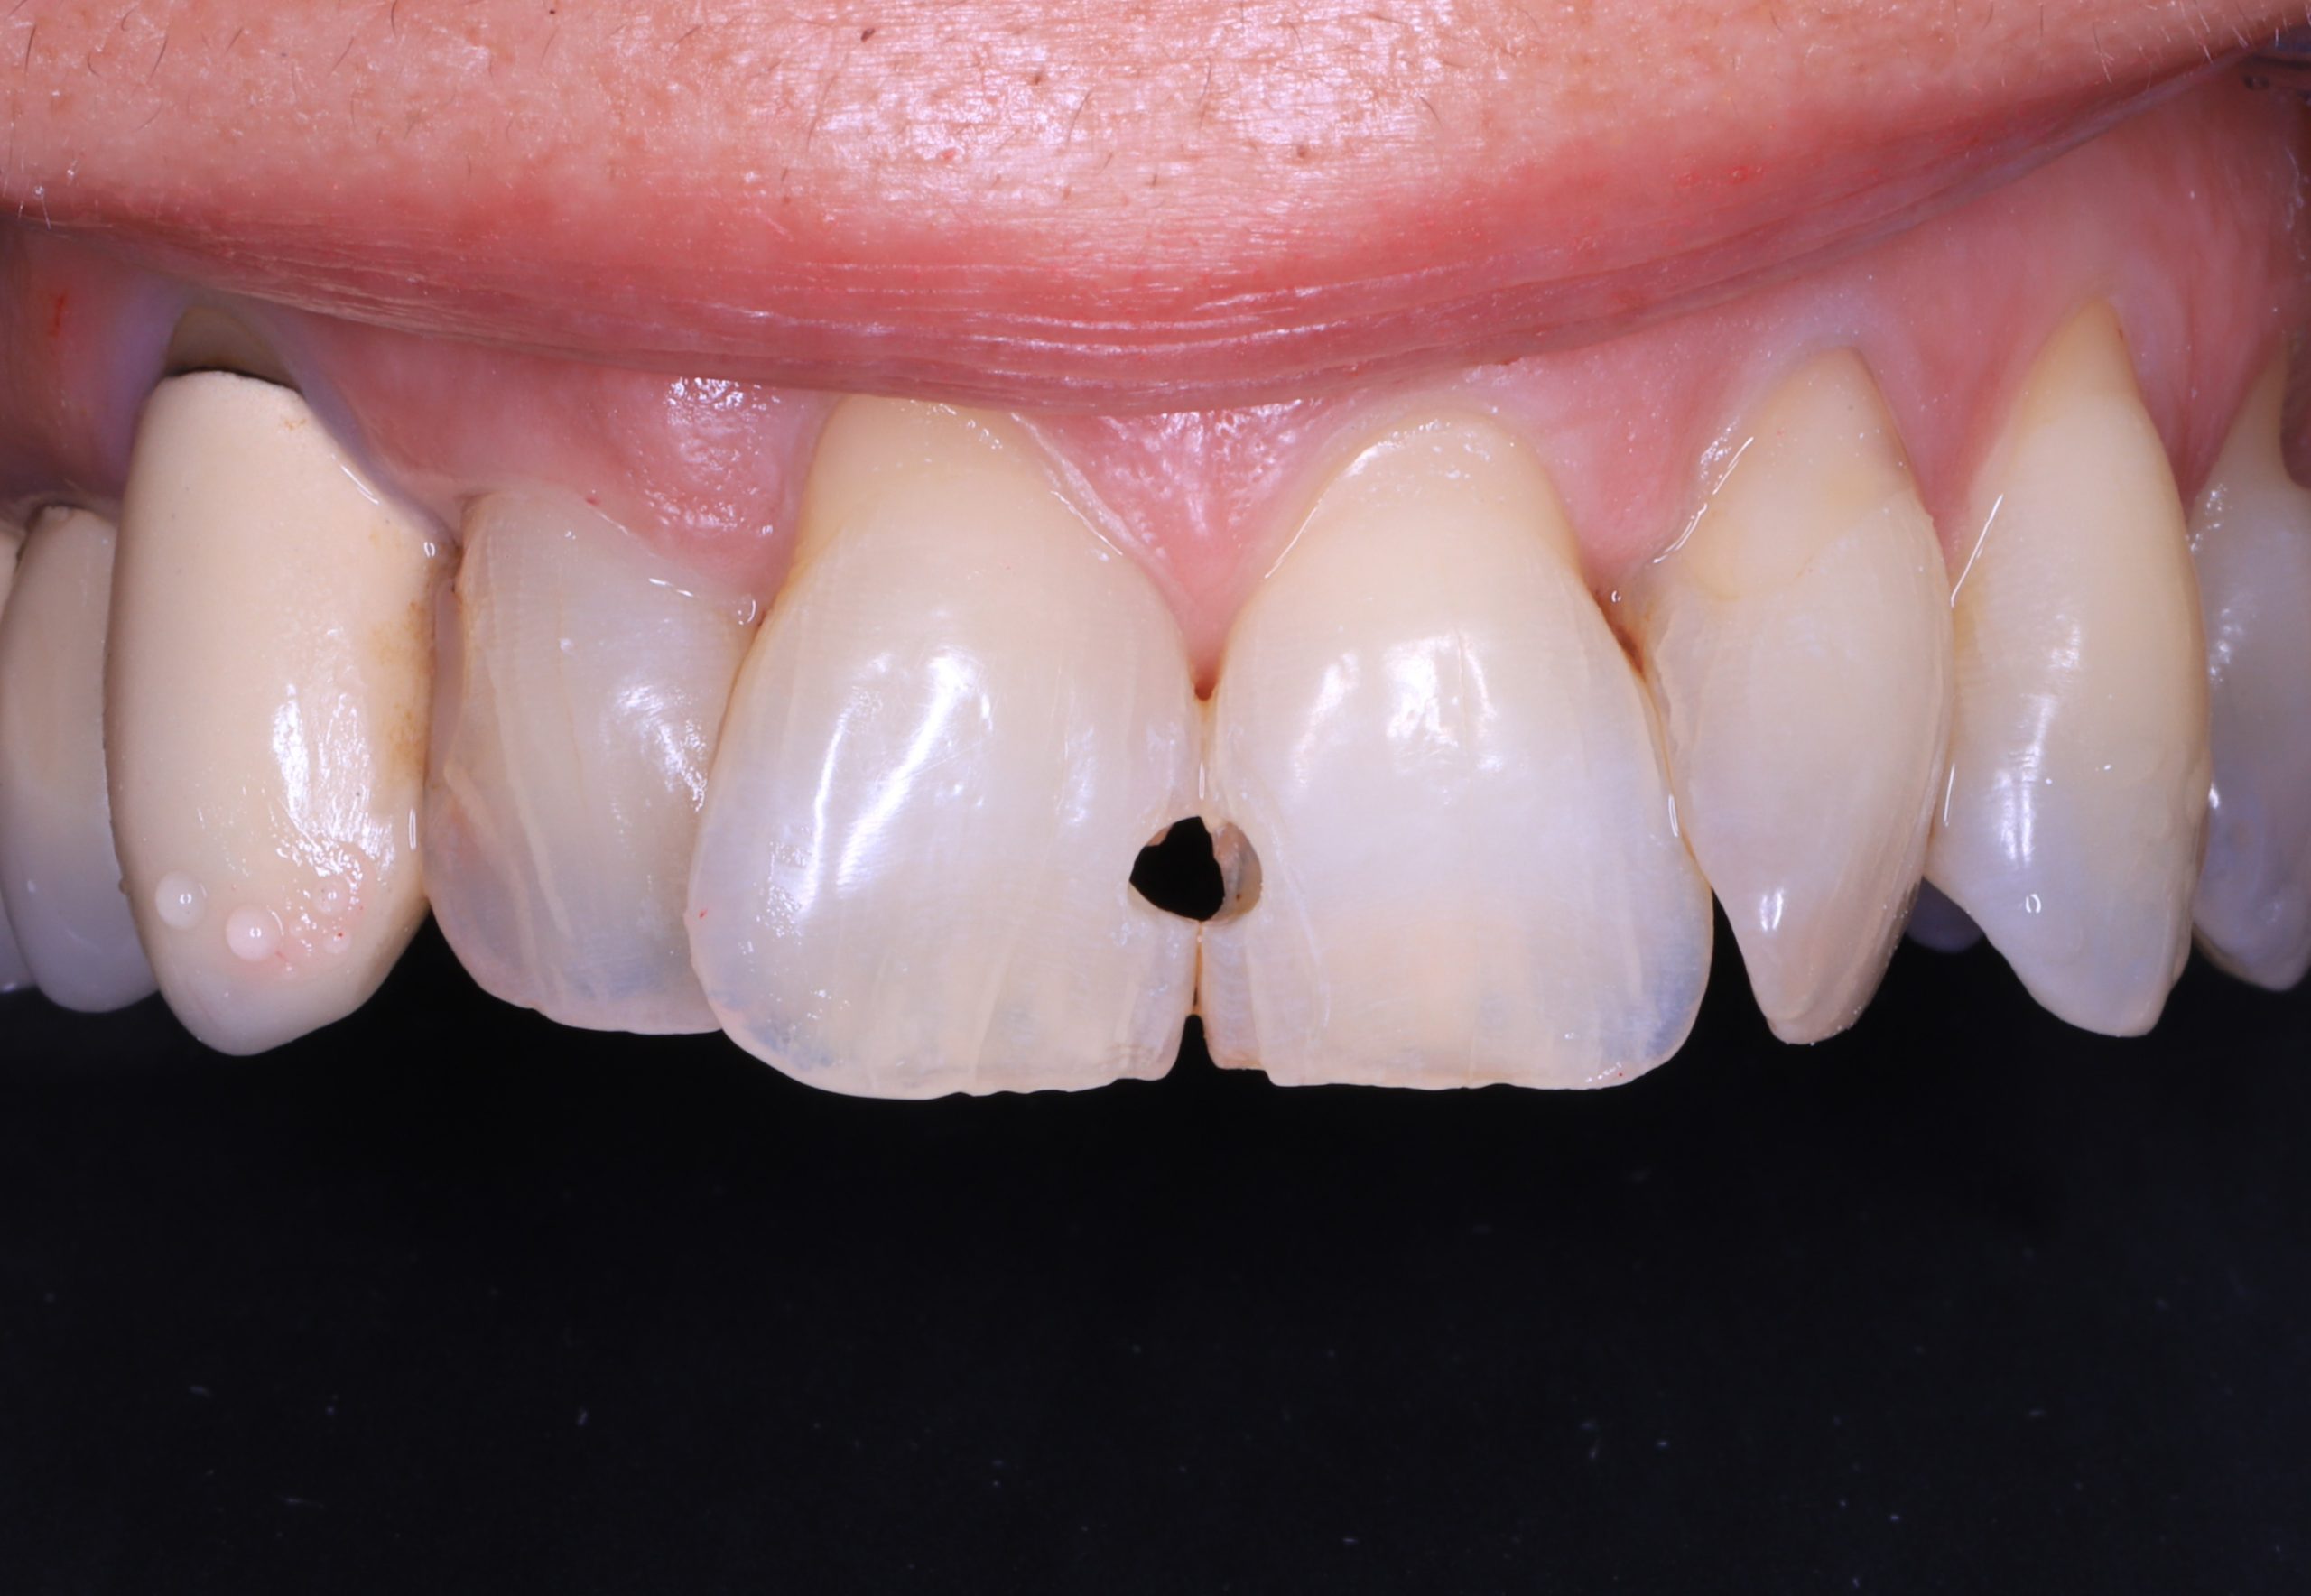

1. Preparation of the Tooth

We remove weakened or decayed tissue and clean the area thoroughly. The goal is to preserve as much healthy structure as possible.

When Composite Bonding Is the Right Choice

Composite bonding is ideal for:

• repairing small to medium cavities

• fixing chipped or worn edges

• closing minor gaps